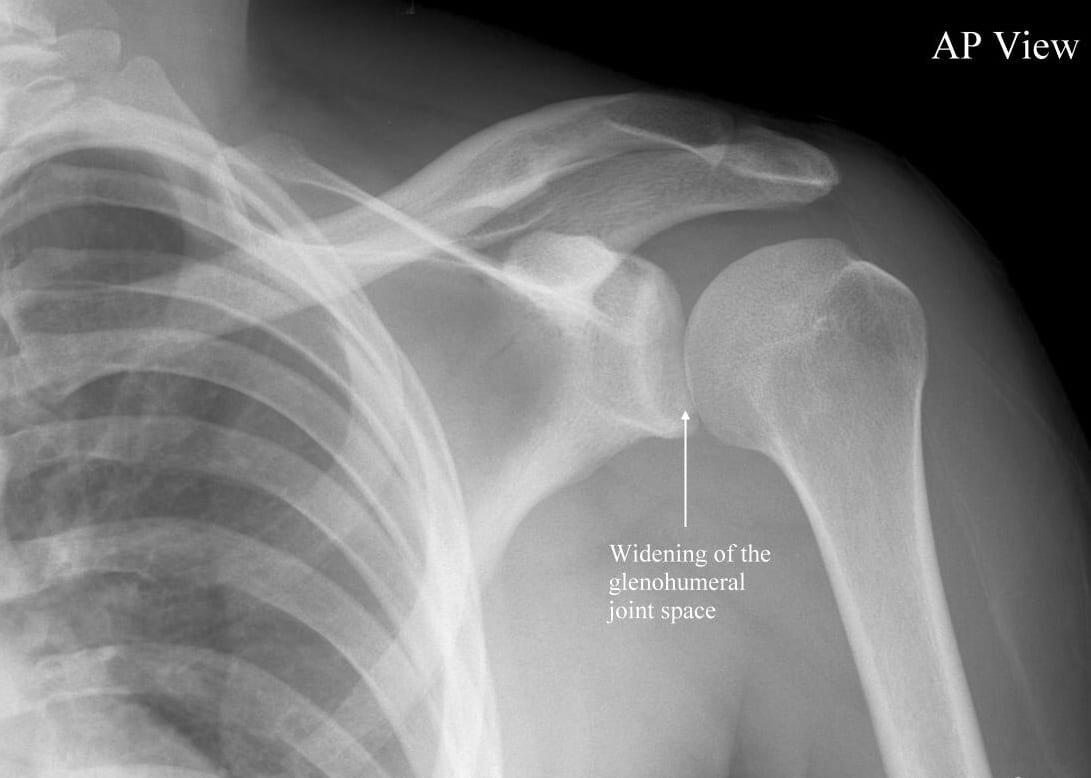

Shoulder dislocation:

Displacement of the humerus from the glenoid cavity due to high velocity trauma on shoulder is known as shoulder dislocation.

Classifications of shoulder dislocation:

1) Anterior dislocationof shoulder (95%).

a) Sub- glenoid. a

b) Sub-coracoid.

c) Sub-clavicular.

2) Posterior dislocation of shoulder (5%).

3) Inferior shoulder dislocation (rare).

3) Carry out an x ray to confirm the diagnosis.